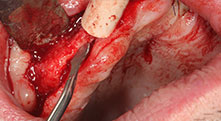

Could you describe briefly, for example, your procedure for mobilizing bone blocks for transplantation?

Bratu: We prefer to harvest bone from the external oblique ridge of the posterior mandible, not from the interforaminal region. After the soft-tissue incision, we use the new saws to define the amount of bone to harvest. With this approach, we also use them for the entire preparation in almost 80% of cases. We may also use other piezo instruments and then at the end a chisel to mobilize the block. We find that this is a very effective surgical technique.

Could you give us a few surgical tips and tricks from your hospital?

Bratu: We like to use the sandwich technique for augmentation in the lateral mandible. A bone cover is prepared with the piezo saw and the crestal fragment is fixed with microscrews. We place a mixture of autologous bone and xenogenic bone replacement material in between. This works very reliably. You should always ensure sufficiently dimensioned vertical cuts when splitting the alveolar ridge in the mandible. Otherwise the bone may fracture easily.